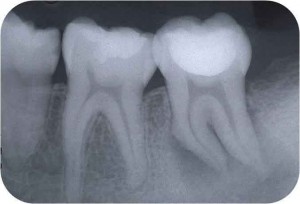

そこそこ細くて弯曲している根管より遙かに難しいのが、写真のような「太くて弯曲している根管」なのです。